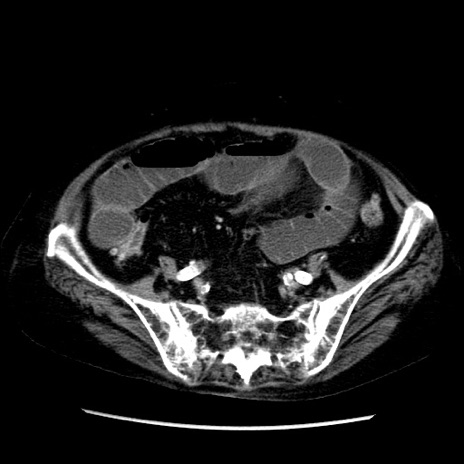

症例14(横断像)

【症例】 90歳代女性

【主訴】 腹痛・嘔吐

【現病歴】今朝から左側腹部痛を認めた。 経過観察していたが、嘔吐を認めたため来院。

【既往歴】 子宮癌術後

【身体所見】 意識清明、BP 127/54mmHg、P 98bpm Sp02 95%(RA)、BT 35.8°C、腹部平坦・軟腸ぜん動音聴取良好、右下腹部圧痛(+) 反跳痛なし

【データ】WBC 9800、CRP 0.46